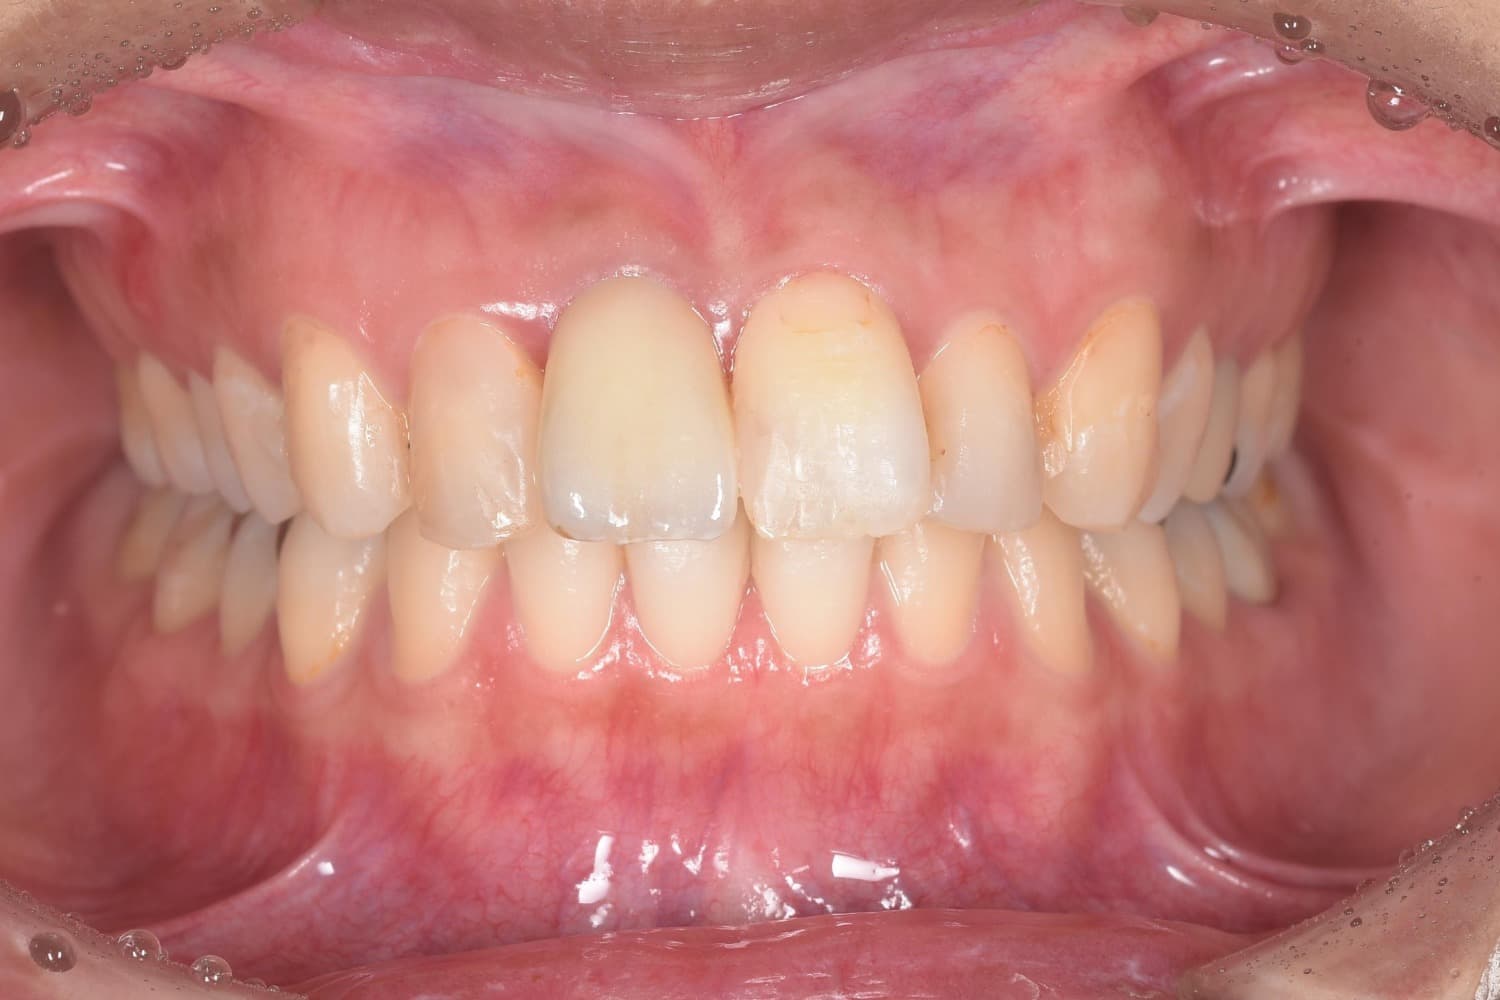

右上1番目のインプラント治療

Before

After

右上1番目の歯を抜歯と同時にインプラントを埋入。 同日に仮歯を装着し、3カ月後にはインプラント上部構造を装着。 インプラント治療により、歯肉のラインを揃え審美的な回復を行いました。

年齢

30代

性別

女性

主訴

右上の前歯が折れた。元々見た目も気になっていた。

治療期間

3ヵ月

治療回数

6回

費用

約47万円

副作用・リスク

インプラントの結合不良、清掃不良による治癒不全